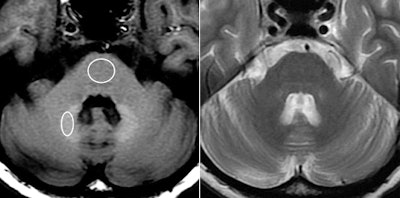

High signal intensity is common in the dentate nucleus and globus pallidus regions of the brain on unenhanced T1-weighted MRI scans, noted lead author Dr. Tomonori Kanda, PhD, and colleagues. Previous research has shown that high signal intensity in the dentate nucleus is associated with a history of brain irradiation or multiple sclerosis, while high signal intensity of the globus pallidus has been linked to a number of conditions, including hepatic dysfunction, calcification, and neurofibromatosis.

Kanda and colleagues also noticed high signal intensity, or hyperintensity, in these two regions in patients who have had more than one administration of gadolinium-based contrast agents.

The analysis showed a significant correlation between the number of previous contrast administrations and signal intensity in the dentate nucleus and the globus pallidus, according to the researchers. Hyperintensity was significantly greater in patients who had received contrast, compared with those who received unenhanced scans.

Increased signal intensity in the dentate nucleus and globus pallidus on unenhanced MRI may be due to the number of previous gadolinium-based contrast administrations, Kanda and colleagues noted.